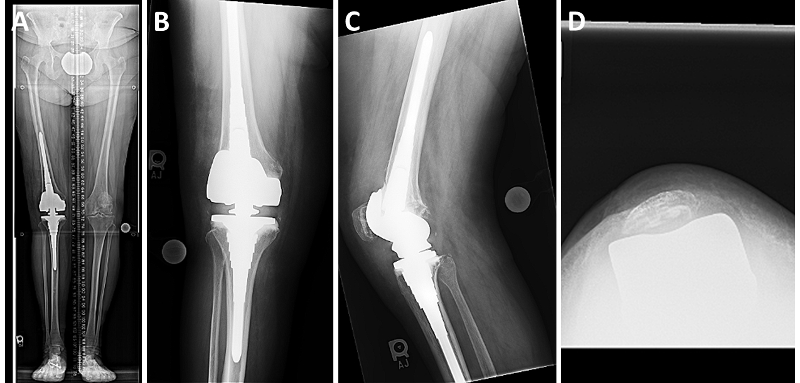

Radiographic examination (Figure 1A-C) showed well-fixed and well-aligned implants, with slight lateral patellar tilt on the merchant view. The posterior condylar offset appeared appropriate, and the implants did not appear oversized.

In this patient, we used single-dose postoperative radiation to prevent recurrence of arthrofibrosis. At four weeks postoperatively, her wound had healed. She achieved full knee extension and flexion to 90 degrees. Her radiographs show excellent alignment in the coronal plane and improved patellar tracking (Figure 2A-D).